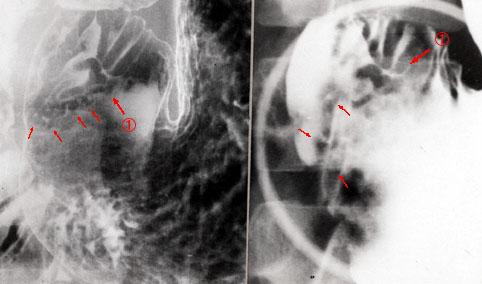

Crohns disease of the intestine with minute gastric lesions.

[ Image ID:4089 ]

Inflammatory or ulcerative disease / lesions/Crohn disease

Stomach/Antrum

X-ray